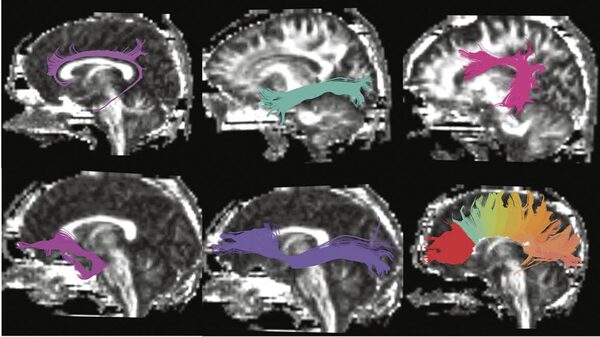

Researchers used diffusion tensor imaging, a form of magnetic resonance imaging, to compare the brains of people with different versions of a gene that plays a role in memory and learning. They found people with one version of the gene had subtle, age-related weaknesses in the white matter connections that form memory circuitry in the brain.

The study involved 69 healthy individuals between the ages of 19 and 82 and combined sophisticated brain imaging and genetics.

Researchers don't yet understand what difference these gene variants make in terms of the disease. But the brain imaging showed that the 41 people in the study who carried the most common version of the gene tended to have subtle but significant differences in brain areas related to memory compared to volunteers of the same age with other versions of the gene.

There were age-related differences in the thickness of the cortex in areas involved in memory, as well as in the white matter connections that form the memory circuitry of the brain.

But this is the first study to use sophisticated brain imaging techniques to show the gene's impact on specific brain structures.